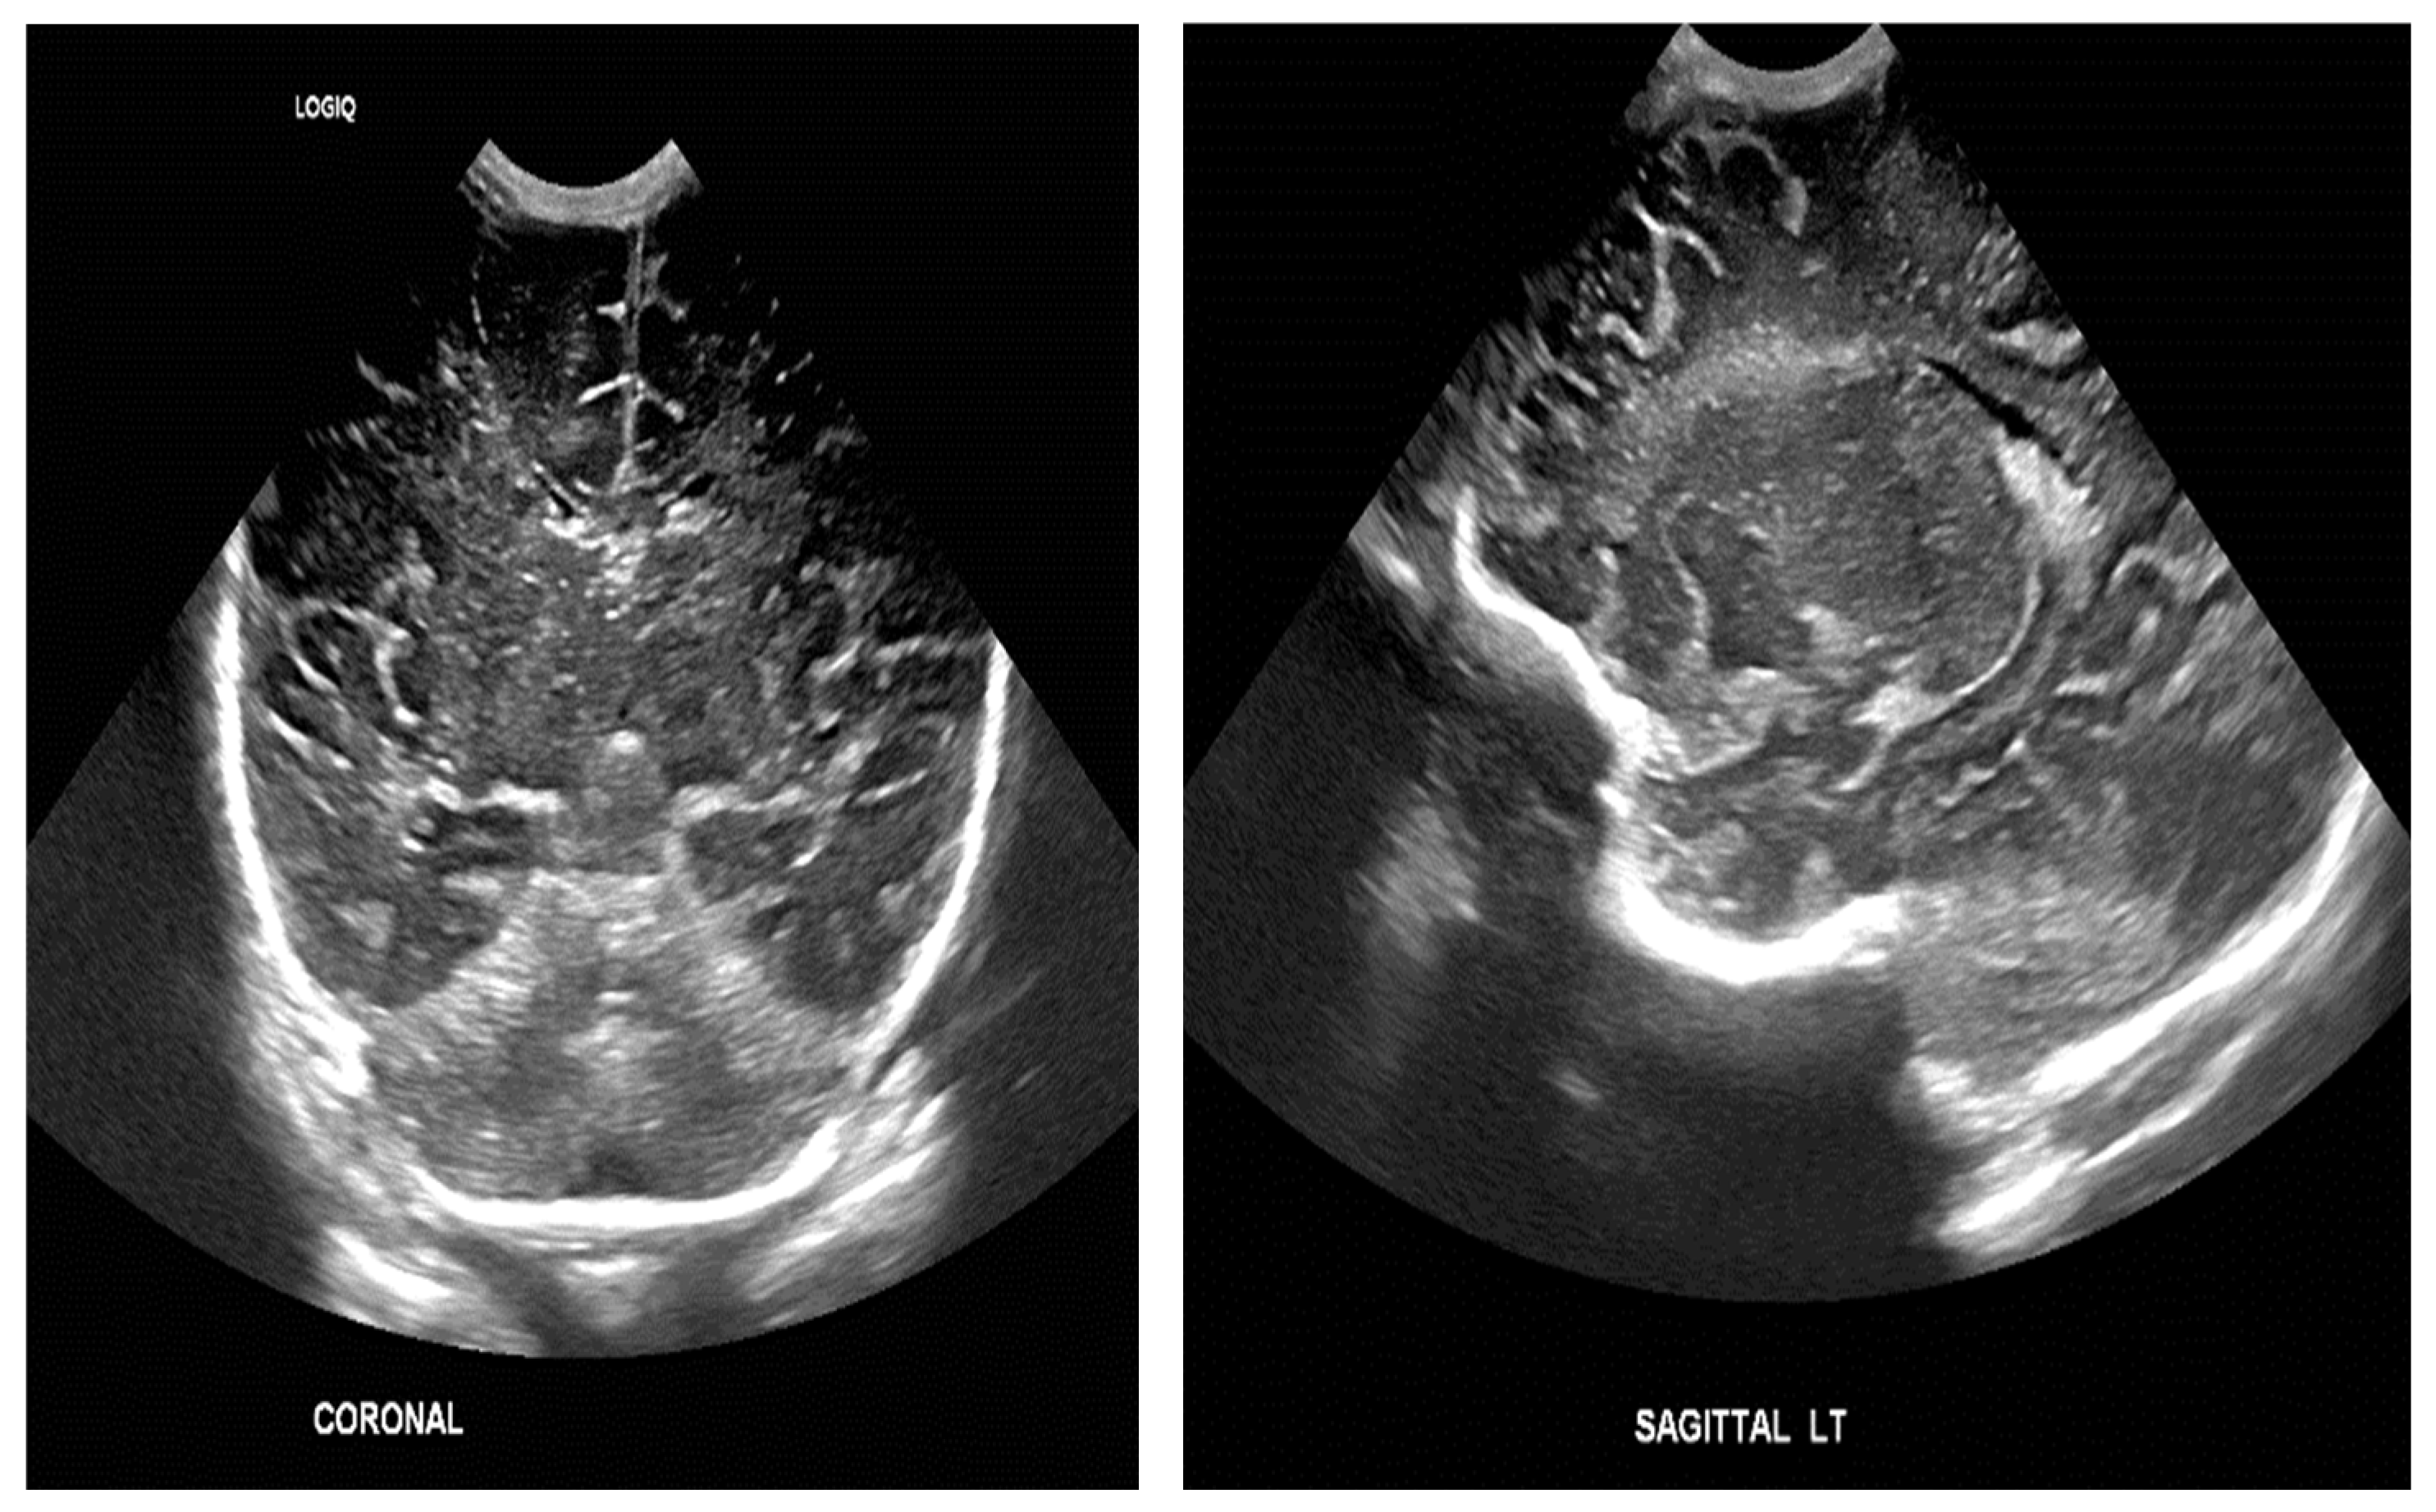

The study population comprised neonates who underwent cranial ultrasound (US) at King Fahad Hospital of the University (KFUH) in Khobar, Kingdom of Saudi Arabia. Neonatal cerebral ultrasound images were collected for this study. The inclusion criteria encompassed neonates who had undergone cranial US at KFUH, with complete sets of left sagittal, right sagittal, and coronal cranial ultrasound images, and those with confirmed diagnoses of germinal matrix hemorrhage (GMH), as shown in Figure 2. Exclusion criteria included neonates without complete sets of the required cranial US images and patients with incomplete or missing medical records. The study initially considered a total of 582 neonates who underwent cranial US, among whom approximately 40 were identified to have GMH.

Figure 2.

Sample of the dataset ((left): coronal US, (right): left US).